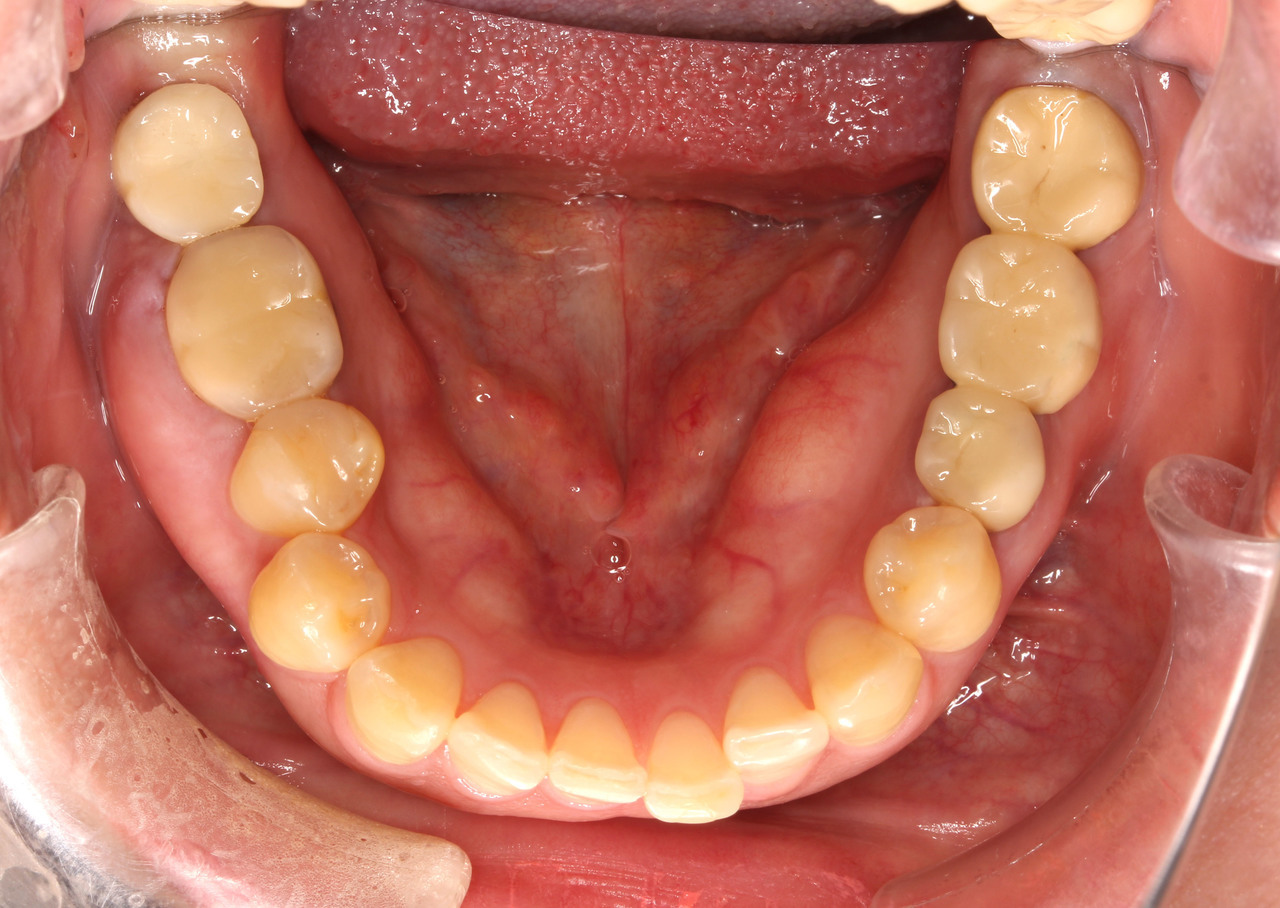

症例3

• 主訴:44歳「ガミースマイルを治したい」という女性で、笑ったとき歯ぐきが出てしまうのがお悩みということでした。

• 矯正方法:マルチブラケット装置(ハーフリンガル矯正)により矯正治療を行いました。

• 抜歯部位:上左右第一小臼歯

• 矯正費用:90万~110万円(税込)

• 動的治療期間:2年

• 副作用リスク:副作用リスクについてはこちらのページをご覧ください。

• ※矯正治療は保険対象外の自由診療となります。